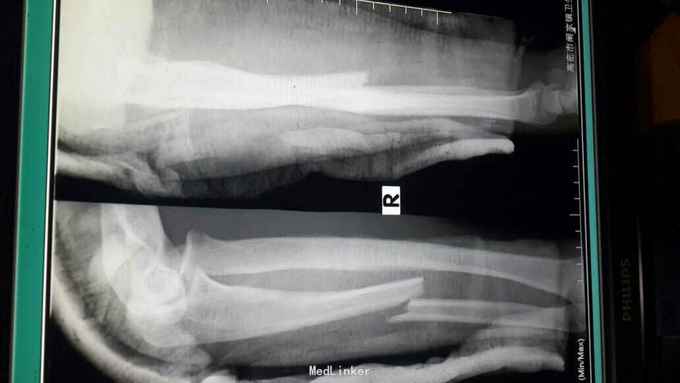

右孟氏骨折

骨折 孟氏骨折

患者,男,21岁。摔伤右前臂肿痛畸形1小时。患者1小时前骑摩托车时不慎摔倒,伤及右前臂,当时即感肿痛畸形不敢活动,院外未治疗来诊。

右前臂肿胀明显,可触及骨擦感及异常活动,肘关节屈伸疼痛,不敢旋转。末梢血供感觉正常。

右孟氏骨折的上尺桡关节脱位如何处理比较好